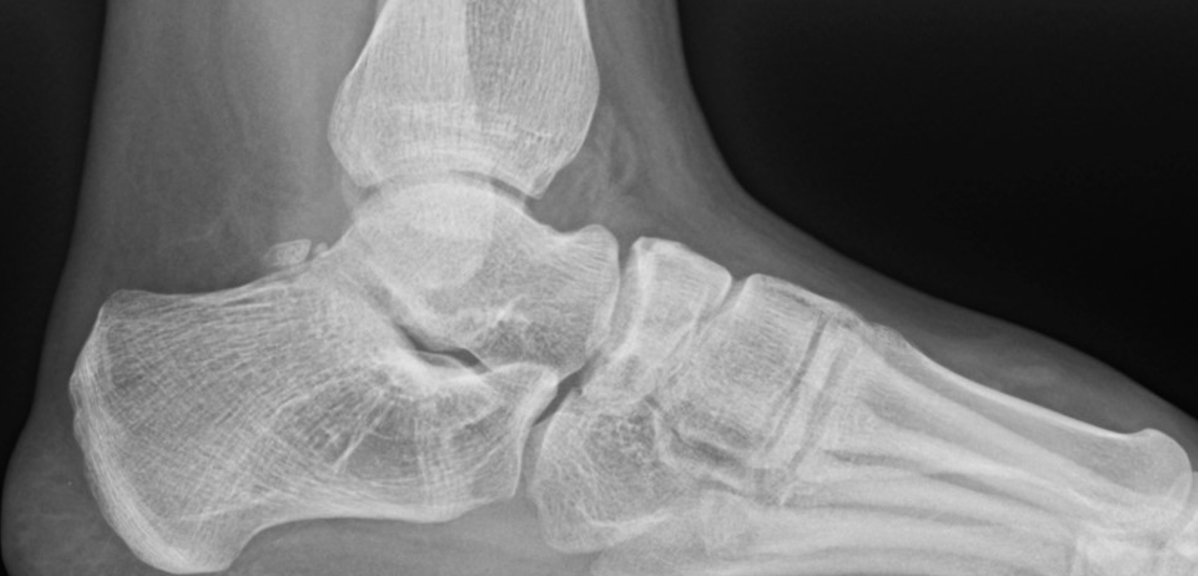

So, to summarize, true congenital clubfeet have abnormal talar bodies, which lead to abnormal ankle and subtalar joints with short Achilles and tight posterior tibial tendons. Regardless of treatment, there is nothing anyone can do to make the talus a normal bone. Many of these cases can and will develop additional deformities. Only the Cincinnati release can address every issue associated with the deformity, but it is NOT a cure. The Ponseti procedure is a total compromise, also NOT a cure. The sooner everyone treats the Ponseti as a compromise, I believe we will be far happier with the outcomes. I remember discussing this with others treating pediatric orthopedic issues during the rise of the Ponseti in the early 2000s. We all agreed, undercorrecting the deformity will lead to more surgeries and residual deformities. Until we all face the reality that clubfeet are a genetic deformity and not just a positional deformity, we will never make them perfect. Thus, athletes and the military will put any and all clubfeet patients to the test. There is no doubt that exceptions exist, but in time, at least based on our limited review of over 1000 clubfeet and 250 cases we saw in the military, no one is immune to complications, arthritis, and ultimately disability.

Here is a typical case presentation. A 21-year-old Marine at Ft. Leonard Wood for training underwent a Cincinnati release at one year old and had stellar follow-up. Her surgeon even wrote her medical waiver for entrance into the Marines. She ran track in high school. She finished boot camp and completed all of her Marine training, but now has chronic pain. She no longer can run. She hasn’t passed her physical training in over a year. She developed talonavicular DJD. By all accounts, her overall clubfoot should be rated an A+; no residual deformity, normal talocalcaneal angles on AP and lateral views, no equinus, no residual varus, only slight met primus elevatus, but no signs of a flattop talus. Clinically, she lacks subtalar range of motion, which I commonly find post-clubfoot release of any kind. So many in the military do very well for a while, but the demands of the military eventually catch up to them. We all root for clubfeet to make it, but the odds are stacked against them.